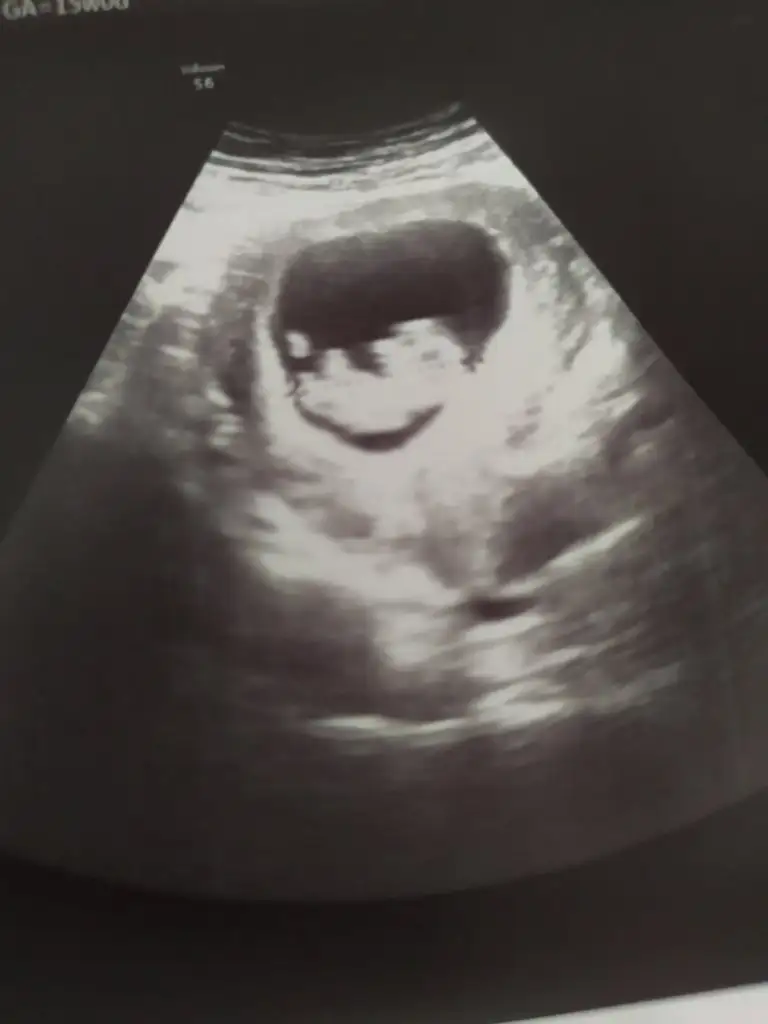

Kızlar bana tahmin yapabilecek arkadaşlar var mı ya ikinci gebeliğim çok merak ediyorum 11 haftalık ultrasyon görüntüsü bu12.haftada ikili tarama testi yapılıyor orda kan veriliyor betayla alakalı Bi değer değil canım sanırım bundan bahsediyorsun unuttum tam değeri ama 50.binin altında kız üstü erkek gibiydi bende tuttu doğruydubu arada gözün aydın sağlıkla al kucağına